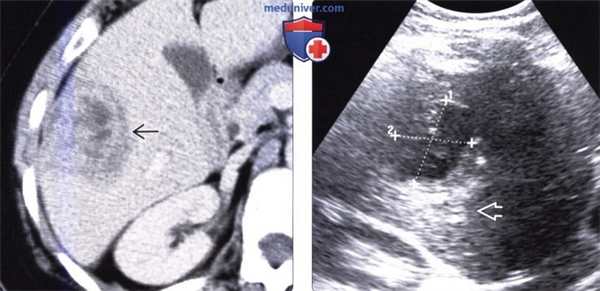

(Слева) На КТ с контрастным усилением определяется объемное образование в печени с гиподенсной центральной частью и «ободком», накопившим контраст-изменения, которые могут быть обусловлены абсцессом или новообразованием.

(Справа) На сонограмме у этого же пациента определяется образование, содержащее комплексную жидкость (стрелки), с акустическим усилением. При игольной аспирации под УЗ-контролем было получено малое количество гноя, по проводнику в полость абсцесса был введен катетер. При повторной КТ, выполненной спустя два месяца, (не продемонстрирована) абсцесс практически полностью разрешился.